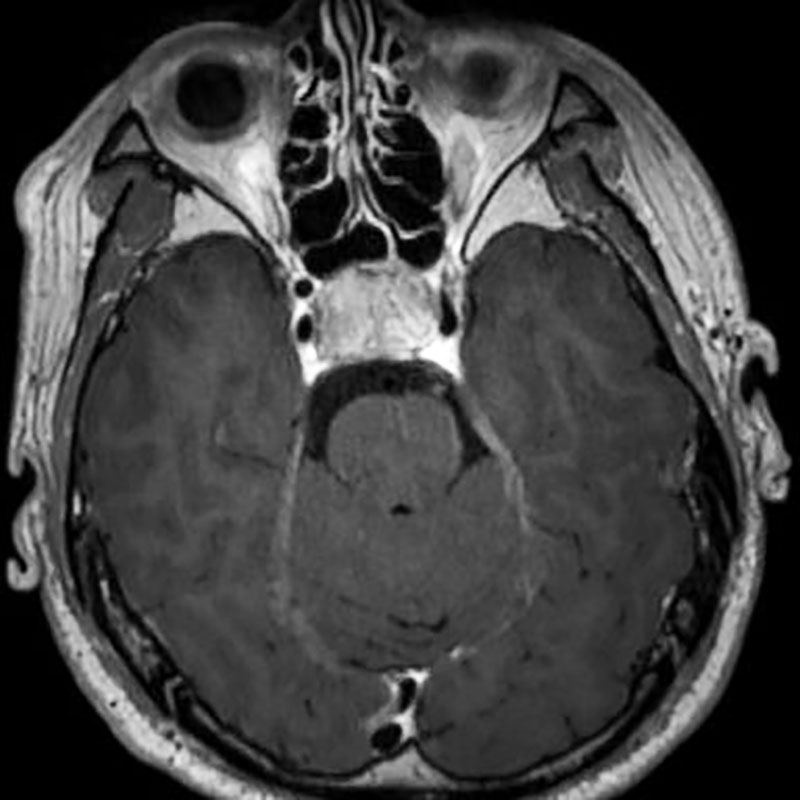

No.’22_12 手術前1

No.’22_12 手術前2